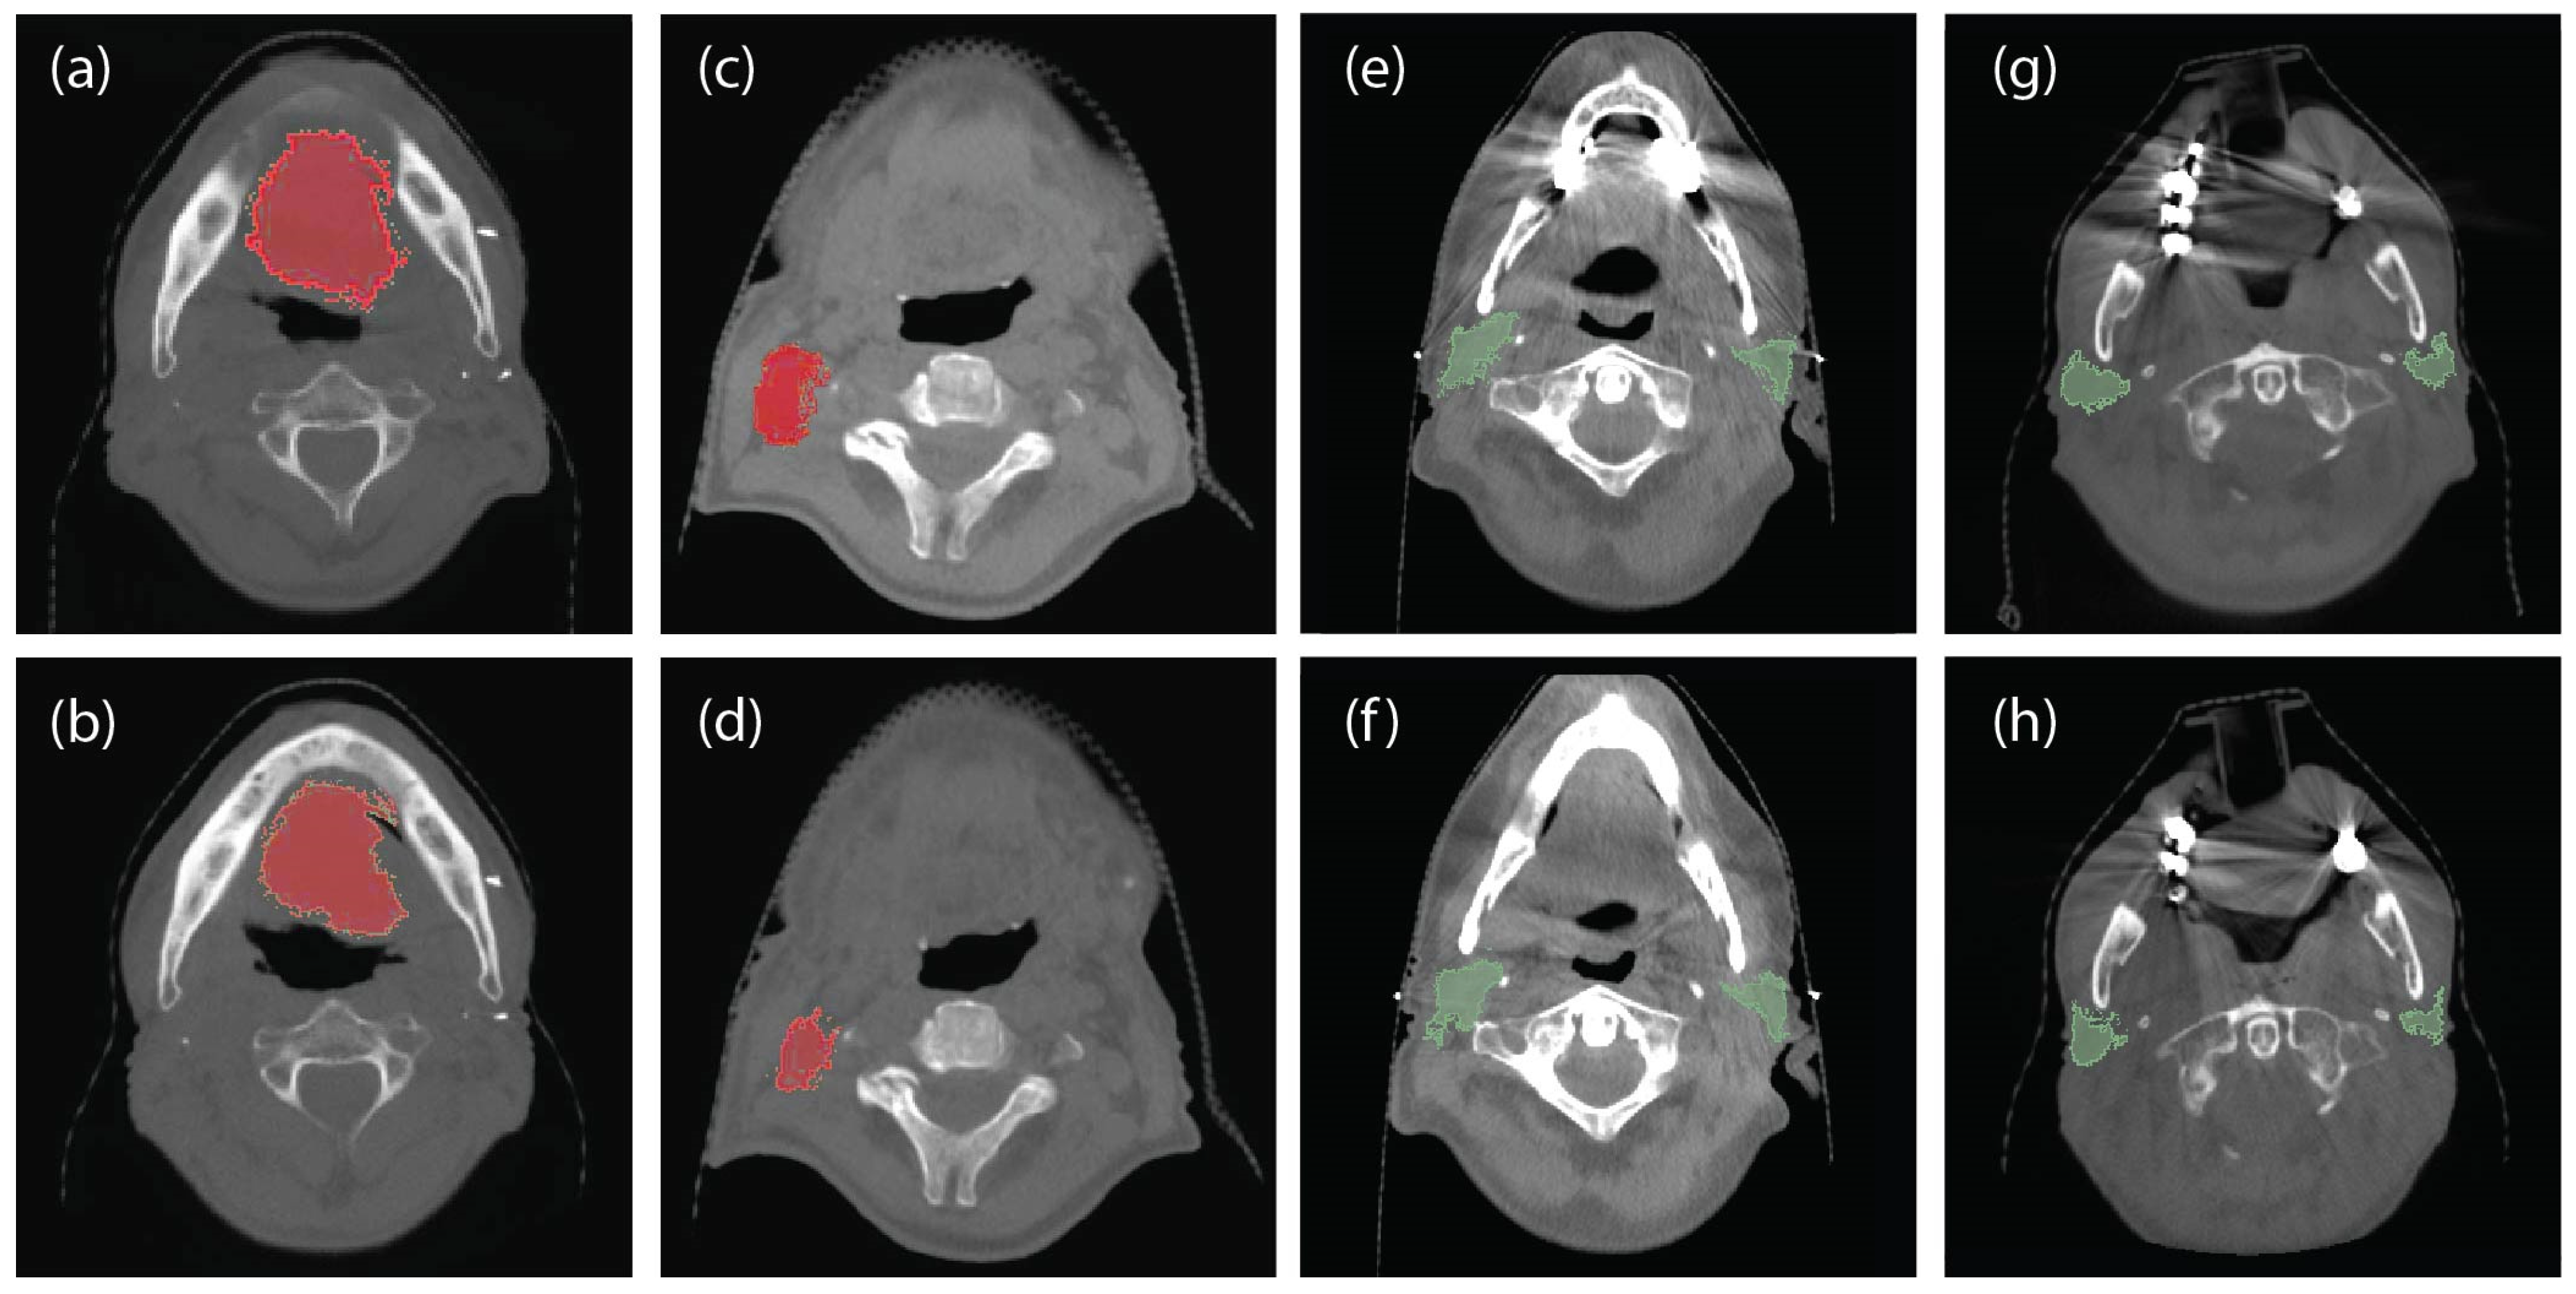

2.2. Data Pre-Processing and Class Designation

2.3. Feature Extraction